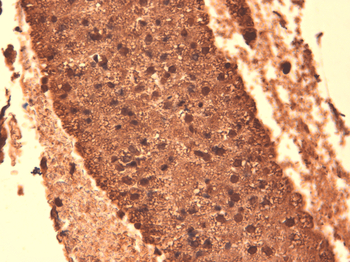

Immunohistochemical staining of paraffin embedded mouse ovary tissue using NIS antibody (2.5 ug/ml)

IHC-P image of mouse ovary tissue using NIS antibody (2.5 ug/ml)